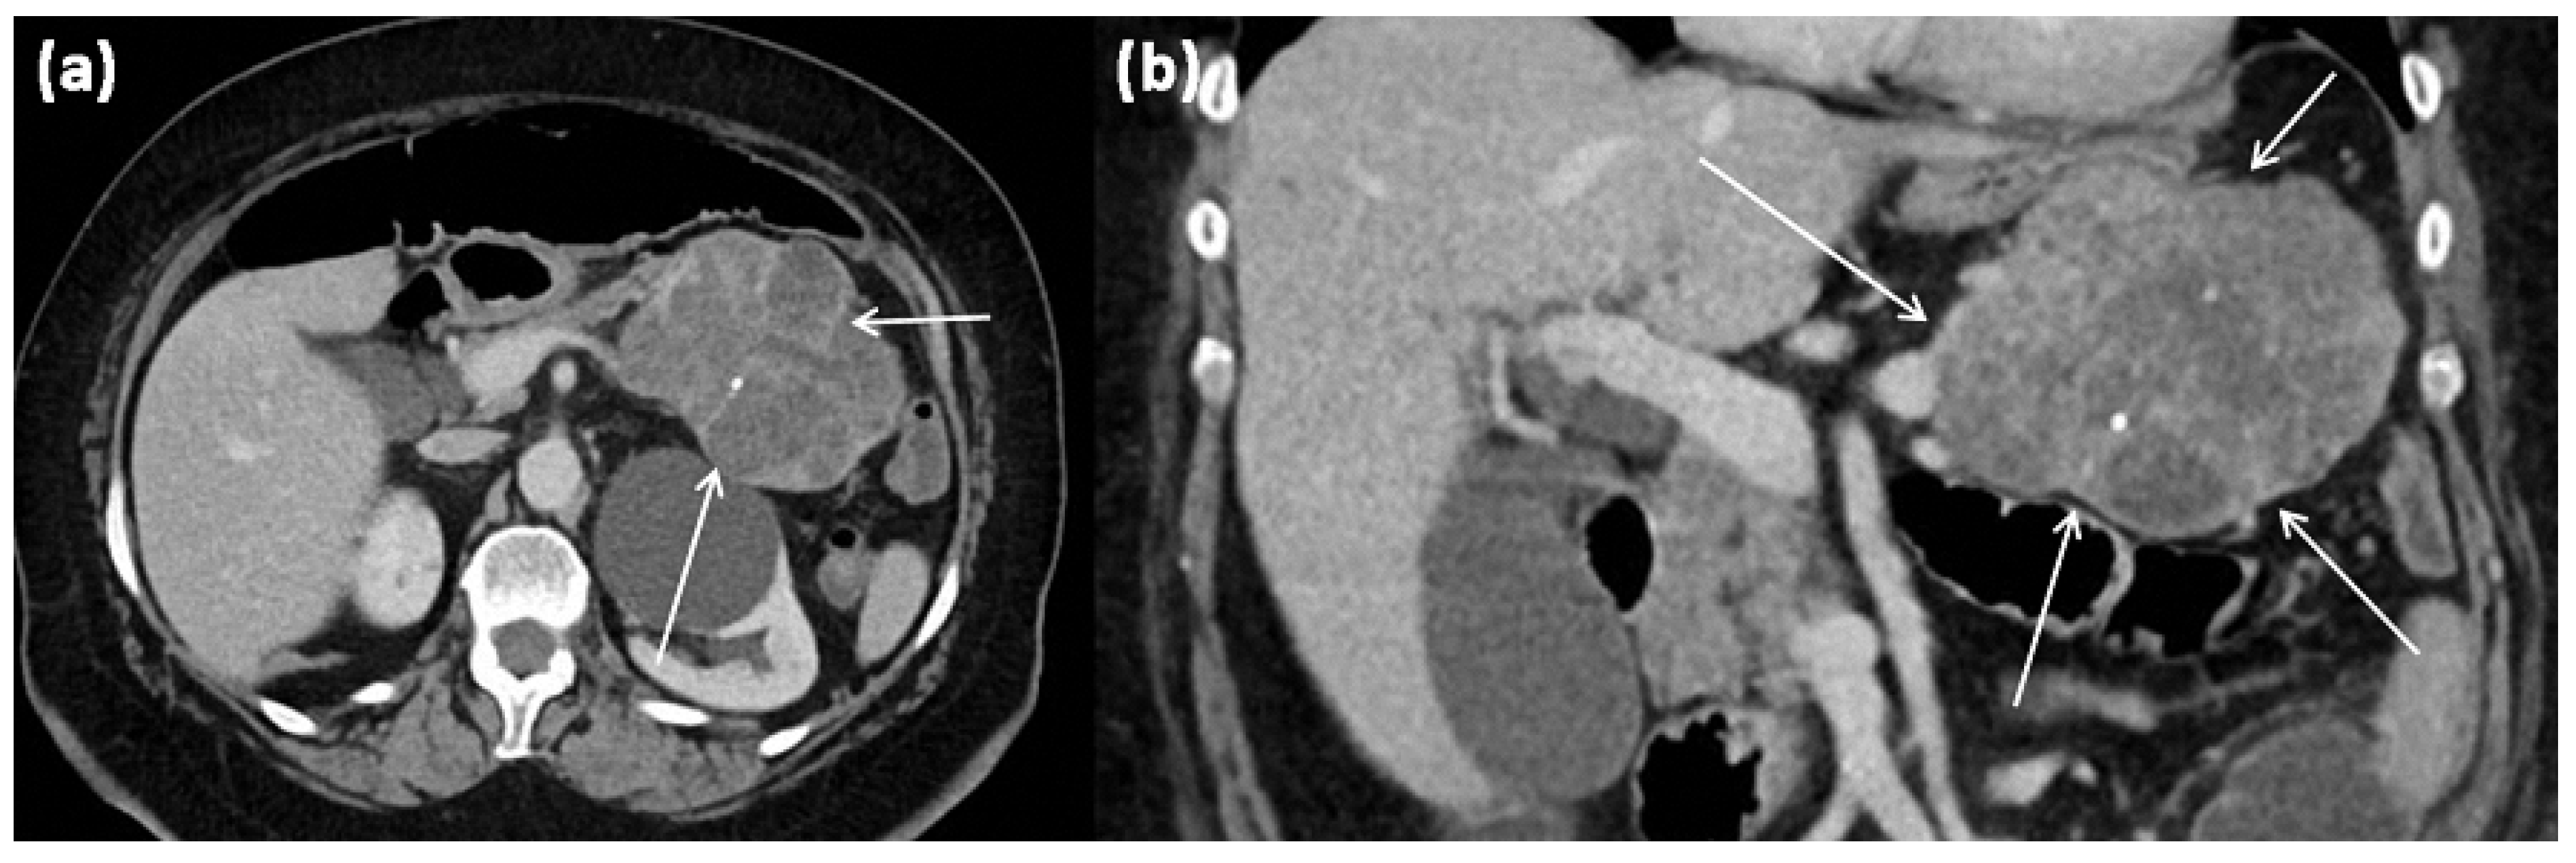

3.4. Cystic Tumors with Solid Portions: Solid Pseudopapillary Neoplasms (SPN)